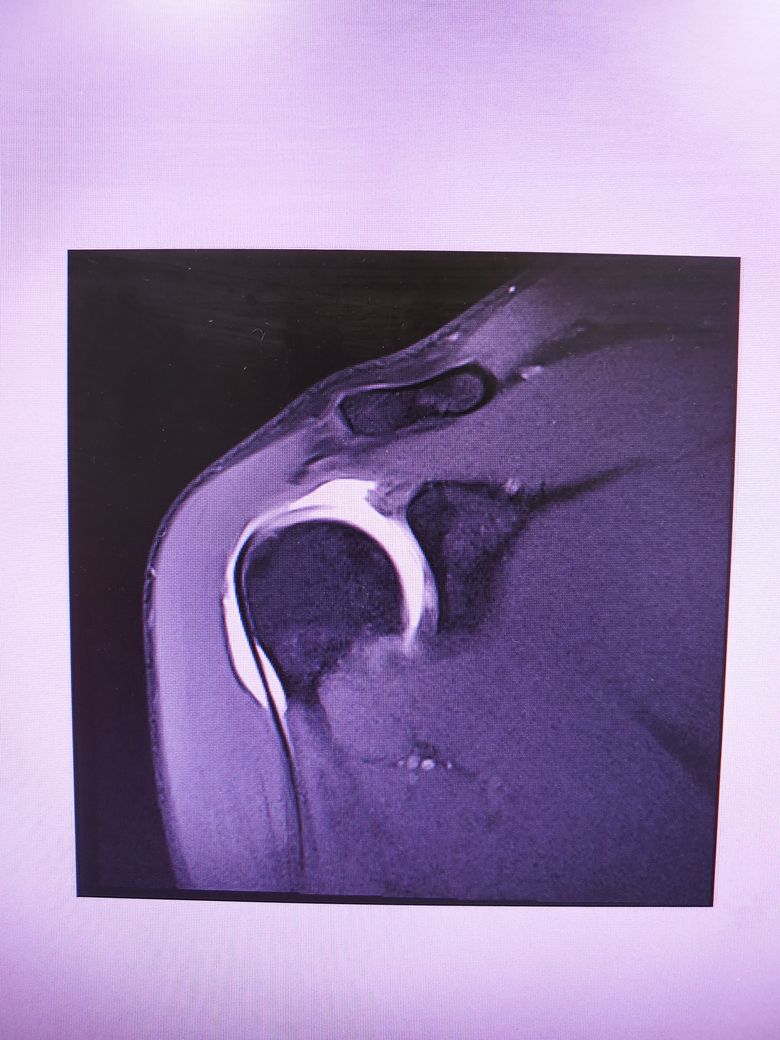

팔이 잡아당겨지는 사고 이후 통증이 지속되어

조영제 투입 후 mri 촬영을 하였습니다.

진단명은 상부관절와순파열(슬랩)이며

헬스와 같은 운동을 계속 하려면 수술이 필요하다 하였습니다.

슬랩이 맞나요? 맞다면 파열 진행 정도는 어느정도인지..

궁금합니다..최대한 사진 많이 올립니다 감사합니다..